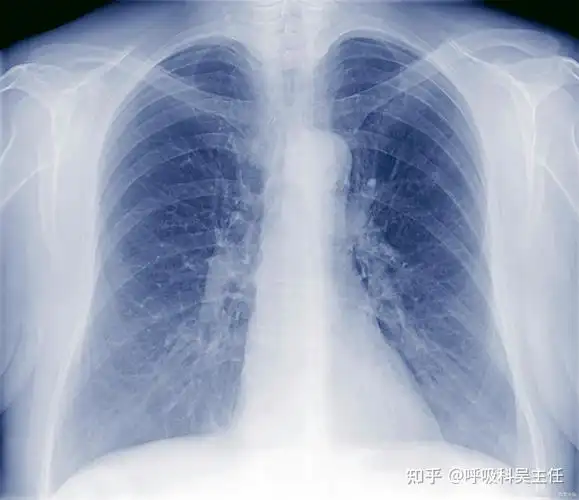

双肺感染是什么意思